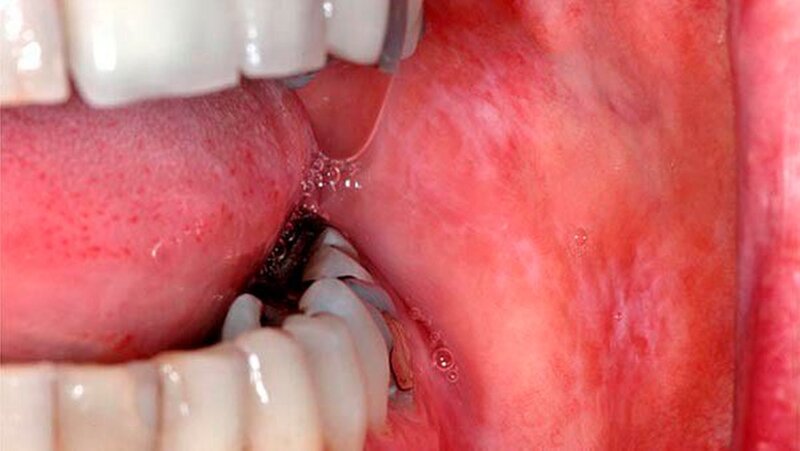

Eine 47-jährige Frau stellte sich Anfang 2012 in der Sektion für Klinische und Experimentelle Orale Medizin am Universitätsklinikum Leipzig wegen länger bestehenden typisch weißlichen Schleimhautveränderungen ohne subjektive Beschwerden vor. Nebenbefundlich bestand eine mit L-Thyroxin behandelte Hypothyreose. Beidseits im Planum buccale und in der Kieferwinkelregion rechts zeigten sich sogenannte Wickham-Streifungen mit stellenweise plaqueartigen Inseln sowie einer schwarzen Pigmentierung vestibulär von Zahn 47 (Abb. 1a, b).

Die Zungenränder zeigten mäßig weißliche papulöse Veränderungen auf. Es lag ein insuffizient versorgtes Gebiss mit zahlreichen großflächigen Amalgamfüllungen und insuffizienten Füllungsrändern mit rauen Oberflächen buccal vor. Im Orthopantomogramm zeigte sich als Nebenbefund eine kleine metalldichte Verschattung projiziert auf das mesiale obere Wurzeldrittel des Zahns 47. Dieser Befund korrespondierte mit der klinisch auffälligen Amalgamtätowierung vestibulär in der Umschlagfalte des Zahns 47. In der zahnärztlichen Allgemeinanamnese berichtet die Patientin von einer erschwerten Weisheitszahnentfernung in regio 48 vor einigen Jahren. Die Amalgamfüllungen und eine Brücke im Frontzahngebiet sind seit über 15 Jahren in situ. Die Mundhygiene war zufriedenstellend.